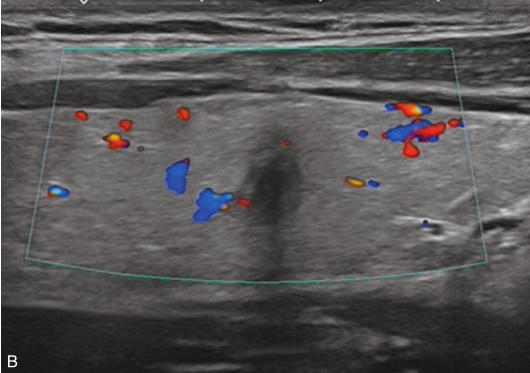

甲状腺囊肿常规超声表现为边界清晰、形态较规则的无回声结节,内可见点状强回声,后伴“彗星尾”征,CDFI内部无明显血流信号,见图1-3-1。

图1-3-1 甲状腺囊肿常规超声声像图

A.甲状腺左叶纵切面;B.CDFI血流图